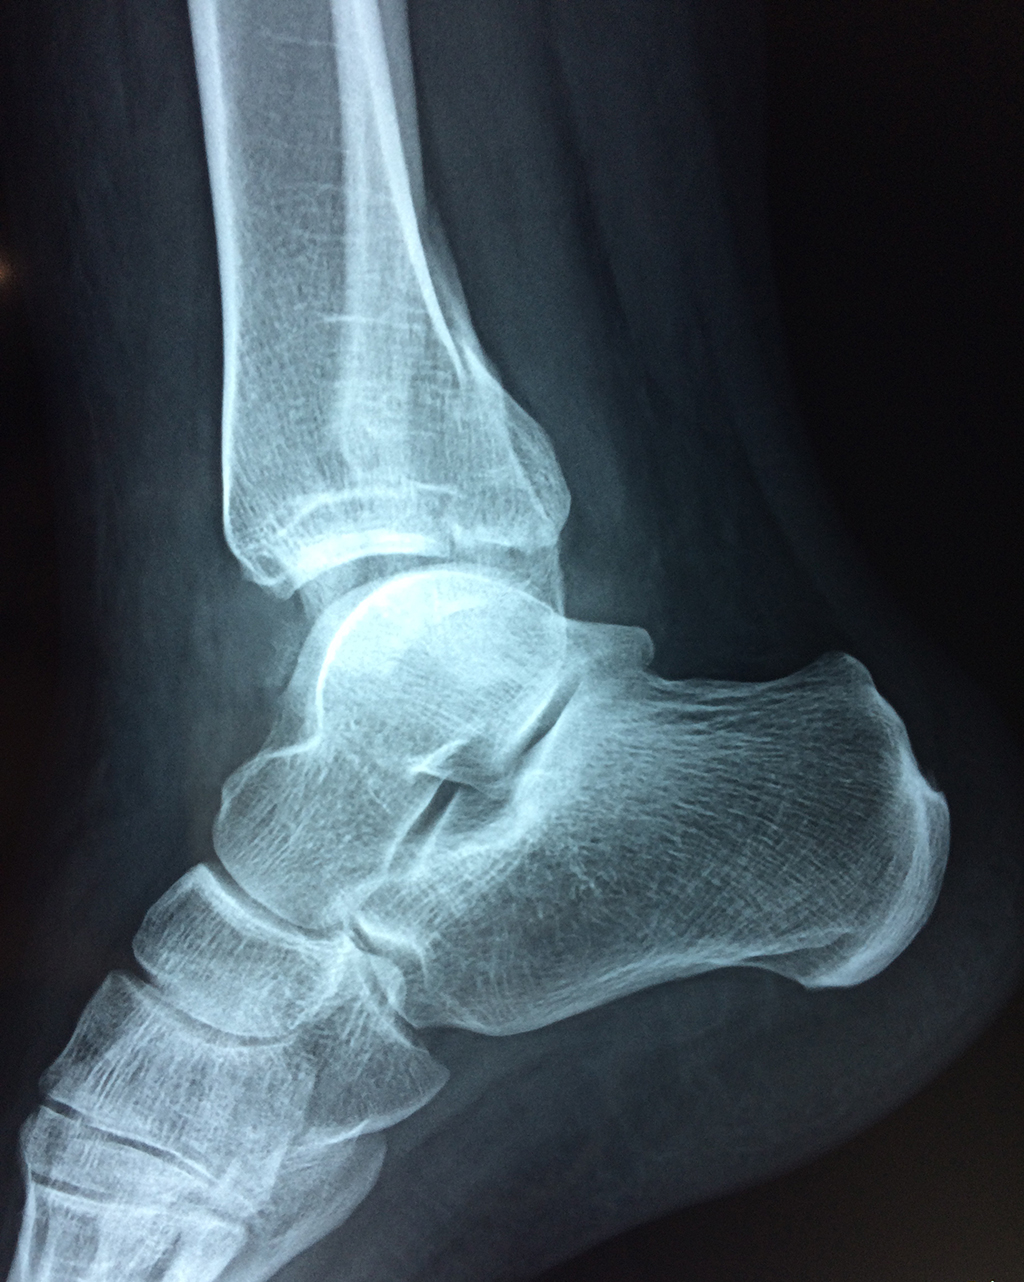

Una fractura de tobillo es la rotura de uno o más de los huesos del tobillo. Estas fracturas pueden ser:

- La fractura se extiende hasta la articulación del tobillo (fractura intra-articular).